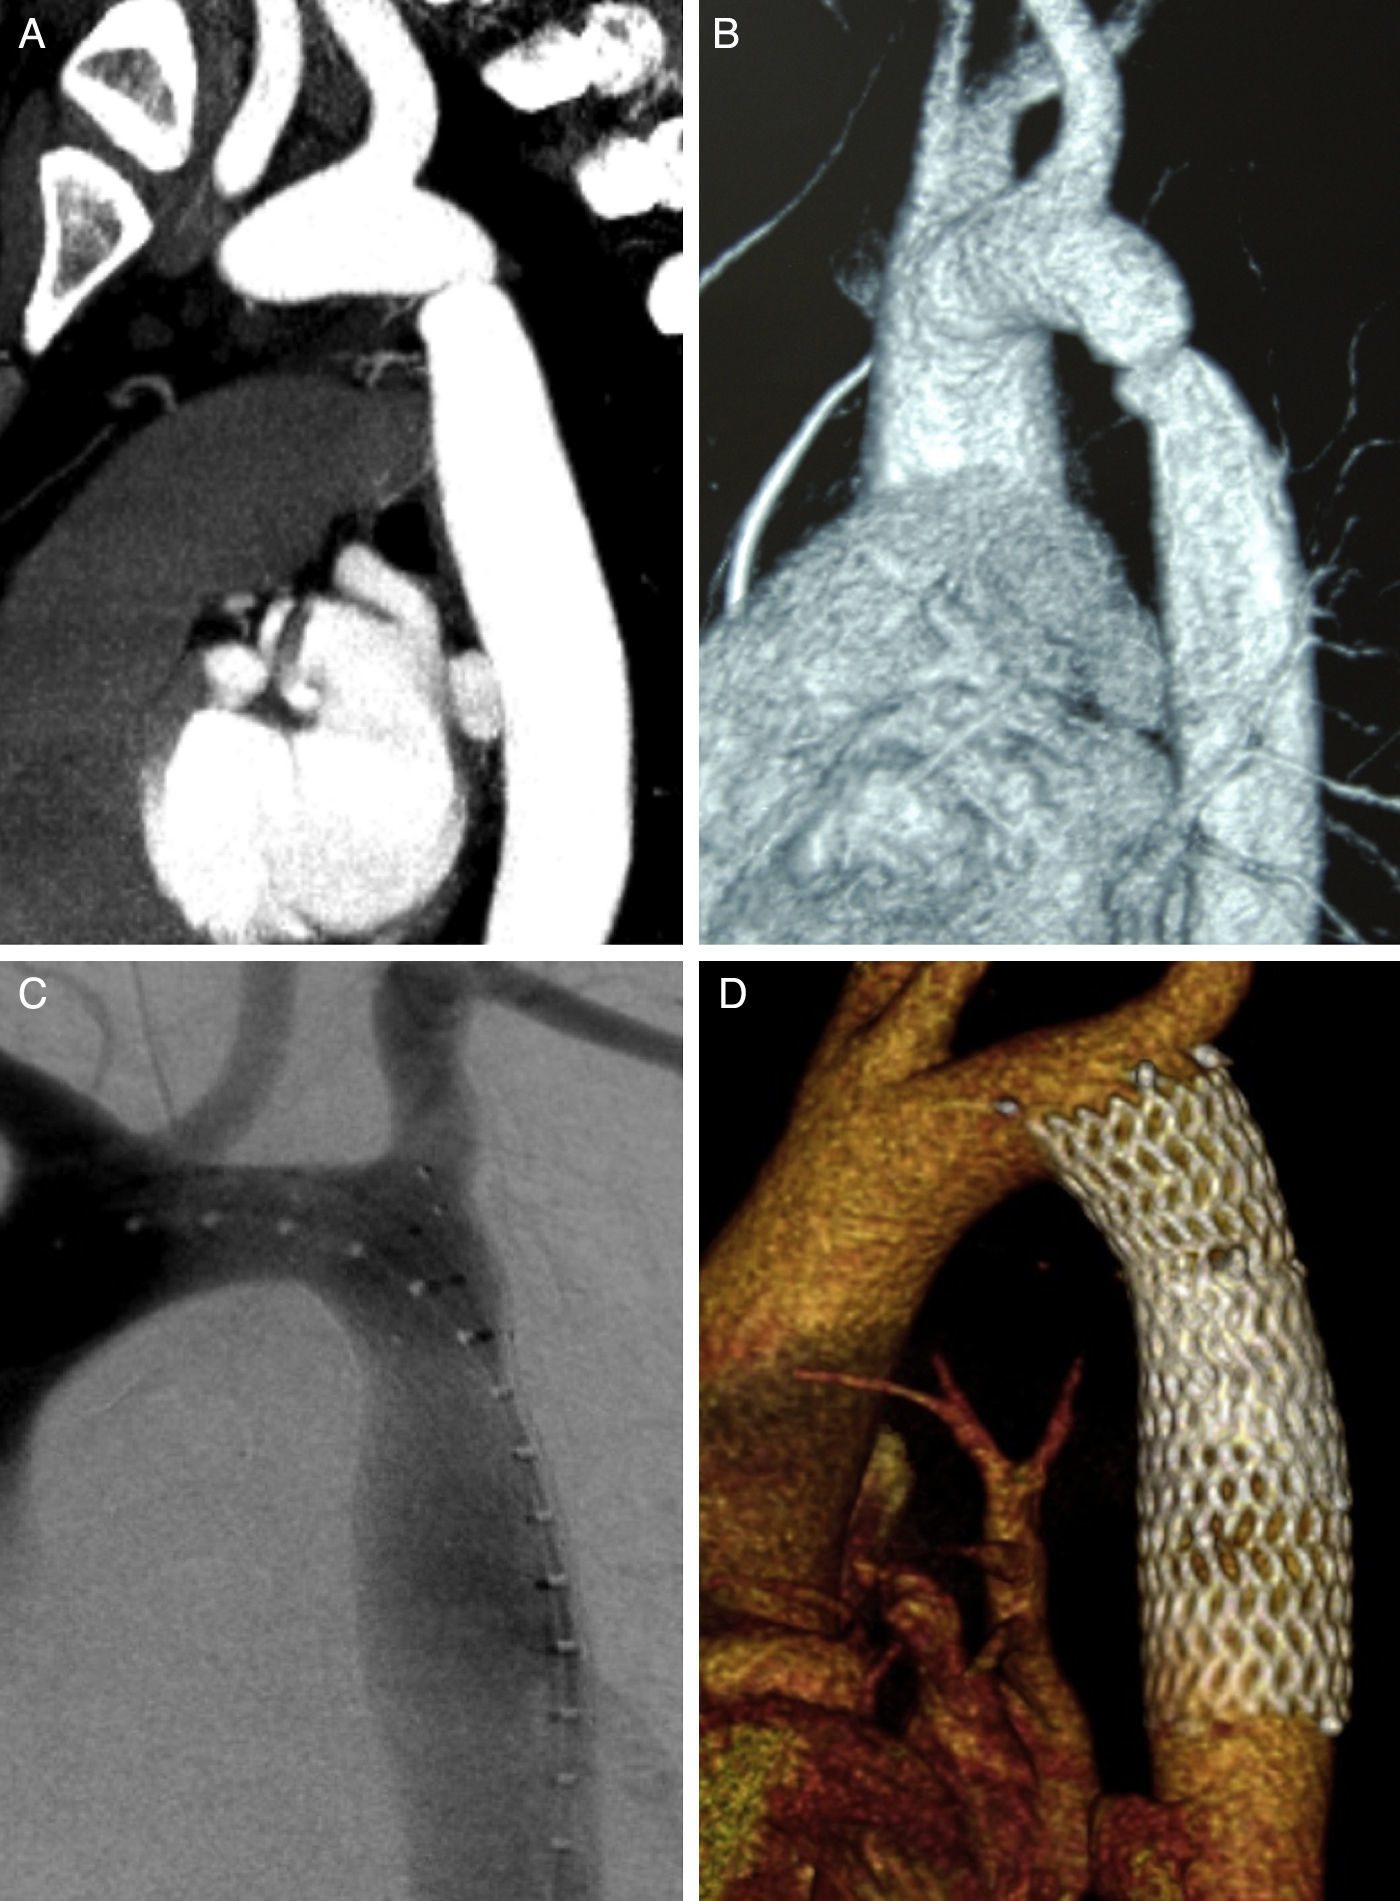

El procedimiento TAVI es una técnica innovadora que utilizo para reemplazar la válvula aórtica dañada sin necesidad de cirugía a corazón abierto. Este procedimiento consiste en insertar una nueva válvula a través de un catéter que se introduce por una arteria, generalmente en la pierna, y se guía hasta el corazón. Una vez en su lugar, la válvula se despliega, permitiendo que la sangre fluya de manera adecuada.

Si tienes una comunicación interauricular (CIA) o un foramen oval permeable (FOP), puedo ayudarte con un procedimiento mínimamente invasivo para cerrar el defecto. Utilizando un catéter, coloco un dispositivo especial que sella de forma segura la apertura entre las aurículas del corazón.

Oclusión de Orejuela Izquierda

Para pacientes con fibrilación auricular que no pueden tomar anticoagulantes, la oclusión de la orejuela izquierda es una solución segura y eficaz. A través de un catéter, coloco un dispositivo que sella esta cavidad, reduciendo el riesgo de formación de coágulos y accidentes cerebrovasculares.